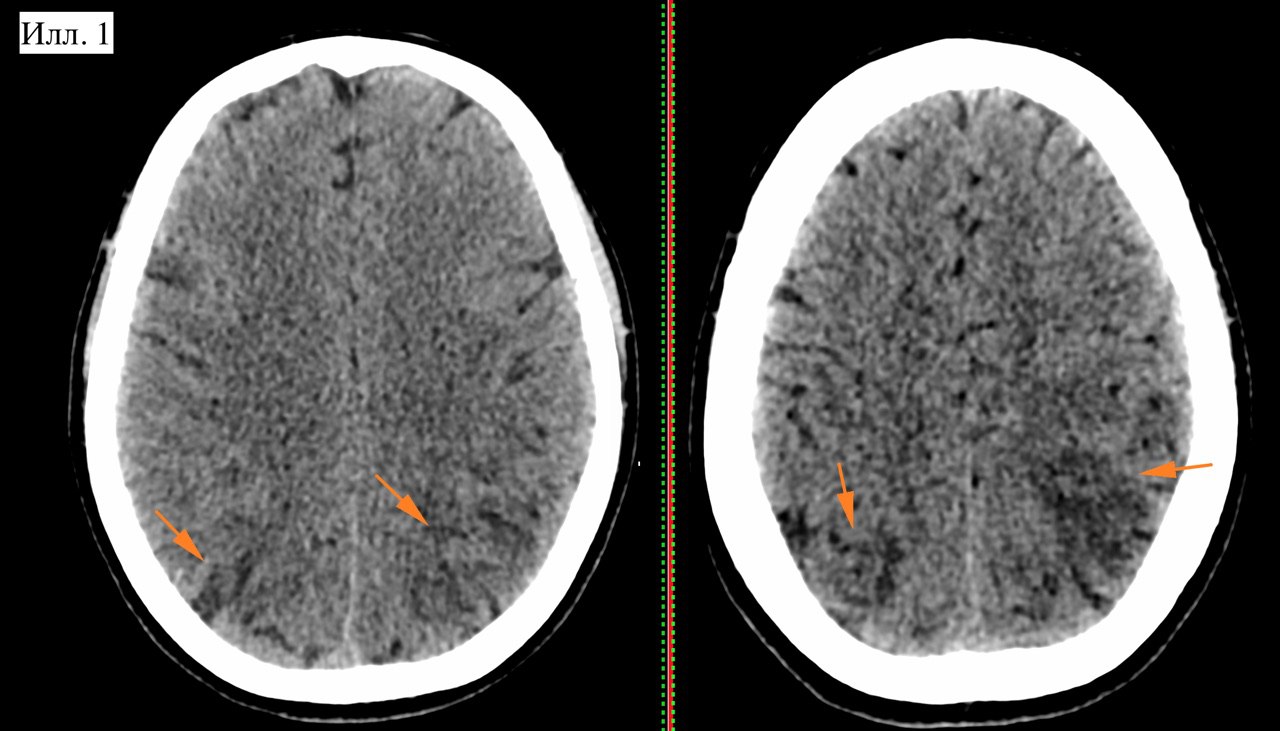

Случай 123. #КТ #МРТ #мозг #ОбучающиеМатериалы #СложныйСлучай

Пациентка Ф., 28 лет. Родильница, с диагнозом «тяжелая преэклампсия». После родов на фоне скачка артериального давления стала жаловаться на слабость, сонливость. Очаговой симптоматики на момент поступления в кабинет КТ не определяли. КТ вызвал ряд вопросов (илл. 1). Определяется несколько зон сниженной плотности в корковых отделах теменно-затылочных зон с обеих сторон (стрелки).

Илл. 1. КТ иллюстрирует множественные фокусы снижения плотности